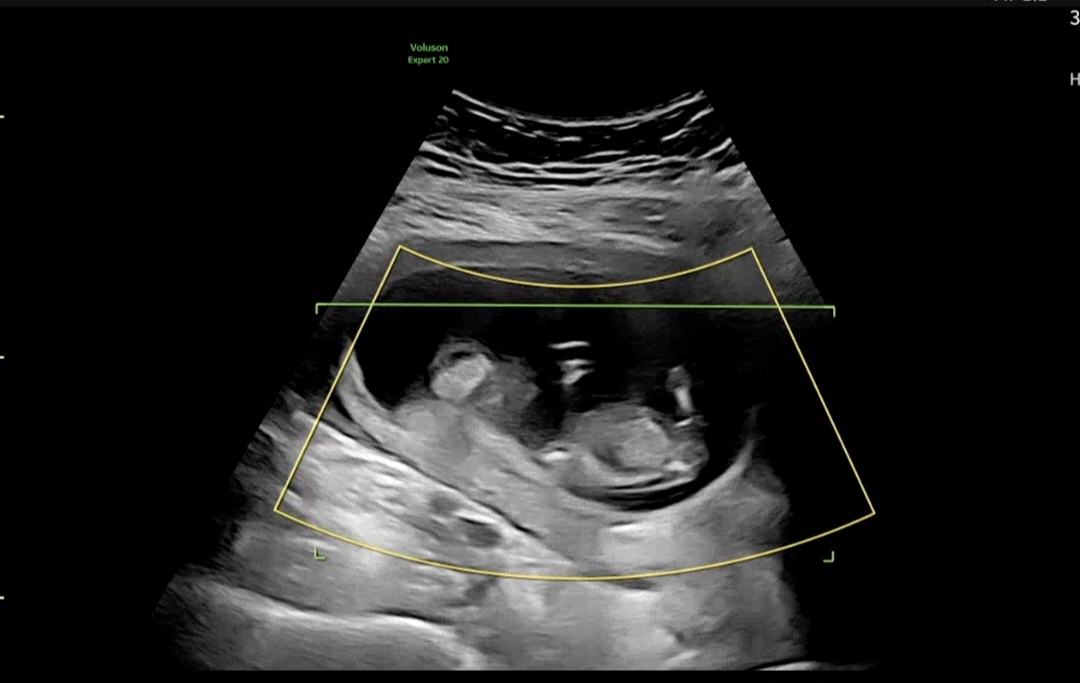

12주4일 각도법 봐주세요 고수님들🧡

오늘 초음파보고왔는데 너무궁금해서 잘안보이더라도 알고싶어요ㅠㅠㅠ 선배님들 잘부탁드려요! 고수님들 알려주세요~~~💛💛💛